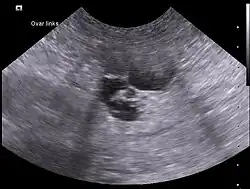

Infolge der östrogenbedingten Ödematisierung kann es in der Läufigkeit zu einem Scheidenvorfall (Läufigkeitsprolaps) kommen. Bei einer verlängerten Läufigkeit empfiehlt sich der Erstellung eines Differentialblutbildes, da erhöhte Östrogenspiegel (Hyperöstrogenismus) aufgrund ihres negativen Einflusses auf das Knochenmark eine Hemmung der Blutbildung, zu Beginn vor allem eine Thrombozytopenie verursachen. Zudem sind eine Vaginalzytologie und eine Sonografie der Eierstöcke zur Abklärung von Ovarialzysten und -tumoren angezeigt.